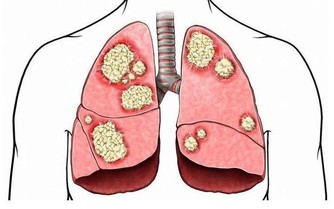

●膝蓋退化了沒!中醫師蔡曜鍵教你自行檢測,還要提供養膝茶飲!還 不快抄起來。